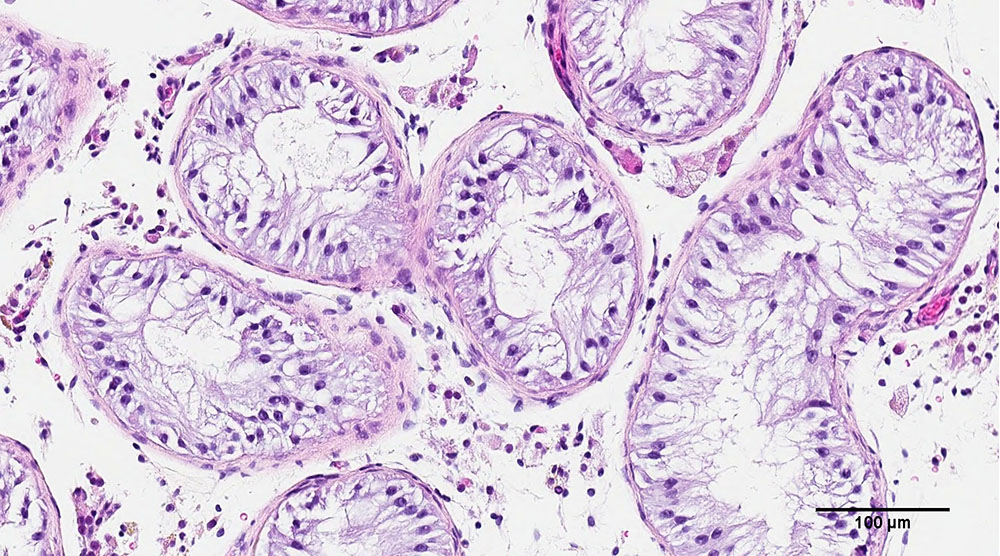

近日,佳士得拍行宣布,波普艺术、20世纪艺术界最有名艺术家之一的安迪·沃霍著名代表作《玛丽莲·梦露》画像,将于5月在纽约界估价将达到2亿美元(合人民12.7亿元),有望成史上第二昂的画作。与此同时,加拿大英属哥伦比亚大学(UBC)的科学家利用3D技术打印出人类睾丸细胞,并发现其有希望产生精子的早期迹象,这是两个“世界首次”。研究团队希望,有朝一日,这项技术能为目前无法治疗的男性不育症患者提供解决方案。

当地时间2022年3月16日,加拿大不列颠哥伦比亚大学(UBC)的科学家们用 3D 打印造出了人类睾丸细胞,并发现了有希望的精子生产技术。